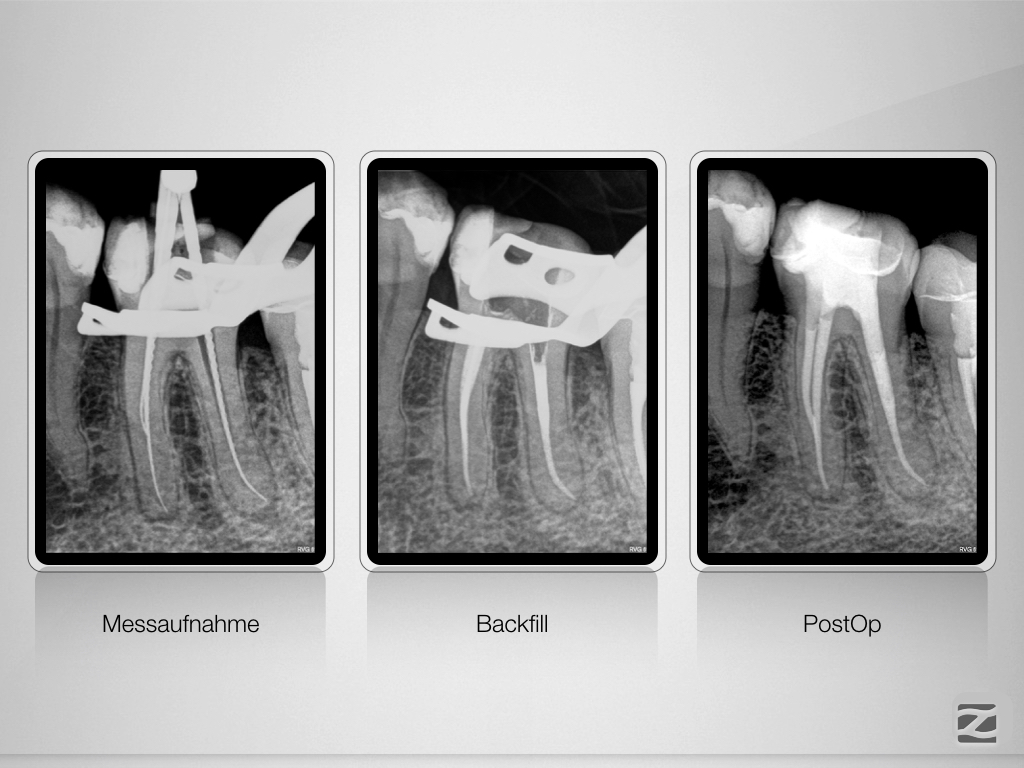

36D.009

Planung leicht gemacht